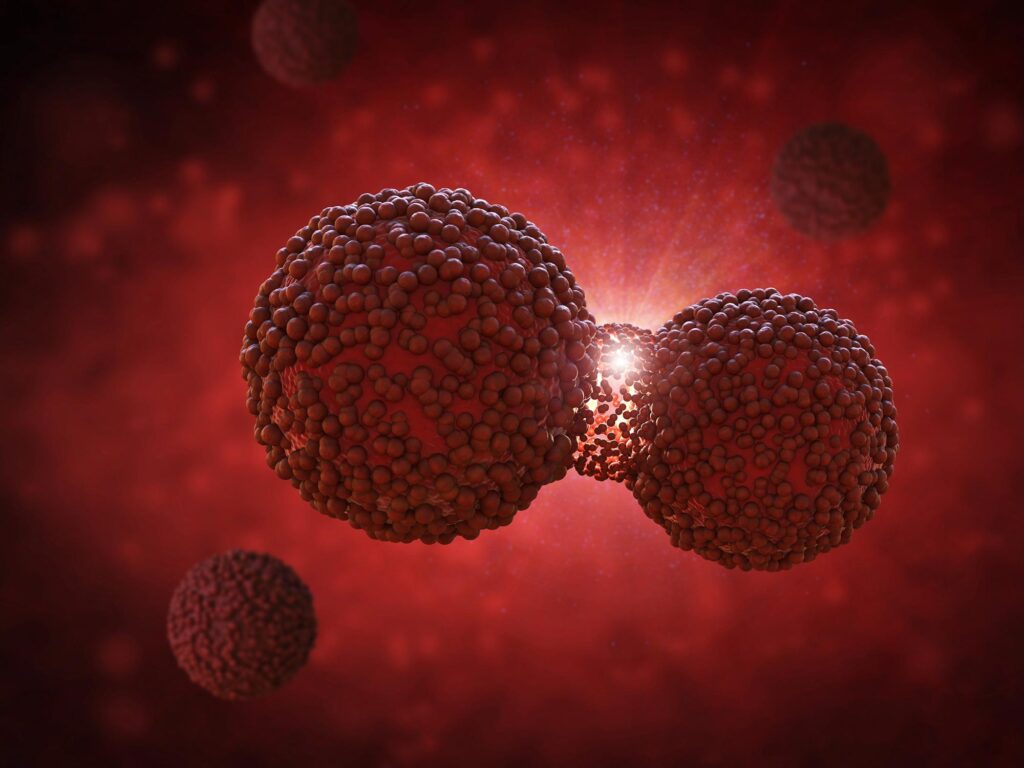

מחקר נטל המחלות הגלובלי לשנת 2021 צופה עלייה בתוחלת החיים העולמית עד 2024-2050, המונעת על ידי אסטרטגיות בריאות ציבוריות יעילות ומעבר בנטל המחלה ממחלות מדבקות למחלות שאינן מדבקות, תוך התמקדות בהפחתת פערים וטיפול בחילוף החומרים ובאורח החיים. -סיכונים הקשורים. התוצאות האחרונות ממחקר נטל המחלות הגלובלי (GBD) 2021, שפורסמו לאחרונה ב- ...